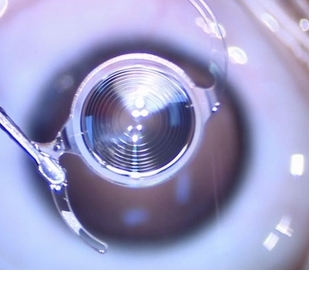

展开与定位:将折叠好的人工晶状体通过推注器经切口送入眼内。进入眼内后,人工晶状体会自动展开并恢复到预先设计的形状。医生会借助显微镜等设备精确调整人工晶状体的位置,使其位于晶状体囊袋内居中且稳定的位置,确保其光学中心与视轴重合,以达到最佳的视力矫正效果。